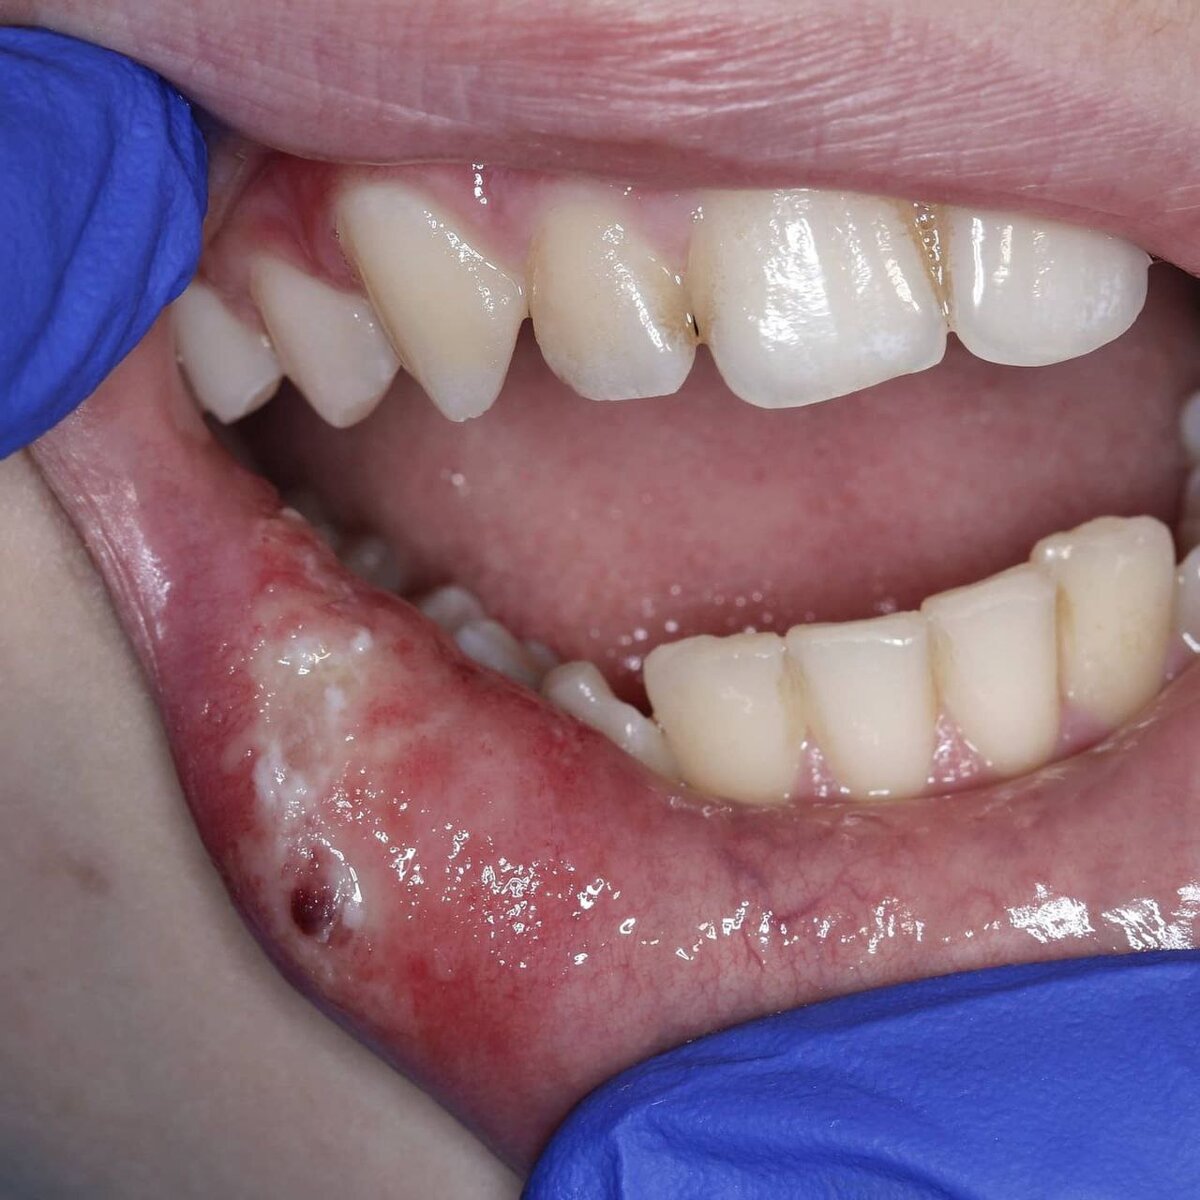

И передо мной открывается картина, примерно как на фото.

Но это не аллергия! Это травма слизистой. Как правило, такое случается, когда ребёнок впервые получил анестезию.

Странные ощущения онемения для него новы, и дитя активно начинает покусывать острыми зубами или посасывать свою губу просто потому что это весело, не подозревая о последствиях! И вот такой итог мы получаем.